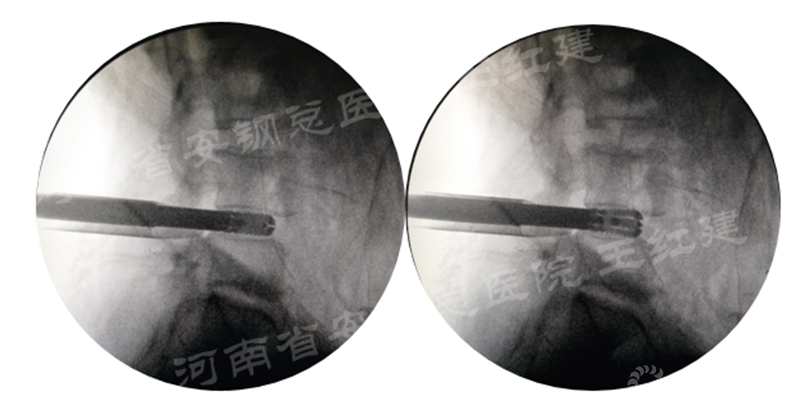

三、通道技术进行植骨、融合

应用通道技术进行植入融合时,首先要更换工作套管,通过枪钳、抓钳的应用处理椎间盘,接着进行自体骨或同种异体骨及cage植入,并通过C臂透视确定试模型号放置融合器,最终完成植骨融合。

确定融合器位置

四、经皮螺钉技术固定

在固定的步骤可以先期进行经皮螺钉置入,再进行融合器的置入,进而实现充分固定。

手术步骤:先期经皮螺钉置入、再进行融合器的置入